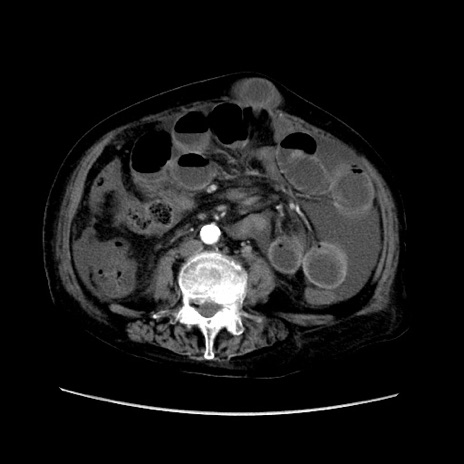

症例31(横断像)

【症例】80歳代 女性

【主訴】腹部膨満感

【現病歴】他院にて肝硬変にてフォロー中。1週間前から便秘、腹部膨満感、臍部腫瘤あり受診となる。

【既往歴】肝硬変

【身体所見】腹部膨隆あり、皮膚変化なし、疼痛なし。

【データ】WBC 4600、CRP 0.25